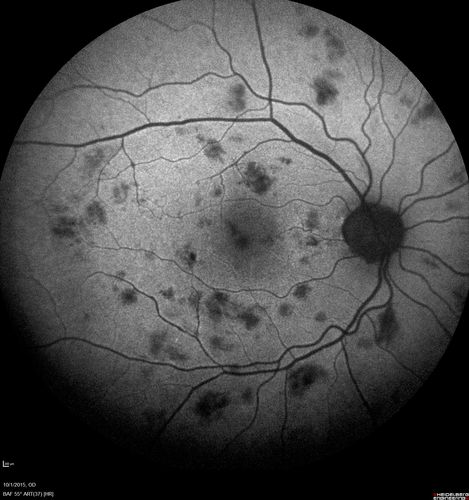

Hairy Cell Leukemia - Retinal Hemorrhage and twig Branch Vein Occlusion

79 year old man He has had hairy cell leukemia since 2002.  He is in remission.  His last blood tests were 9/2018.  He just moved down here and needs a new leukemia doctor.  His vision is fine.

VA OD: Dcc20/25

VA OS: Dcc20/25

IOP: TP: OD:12 OS:12